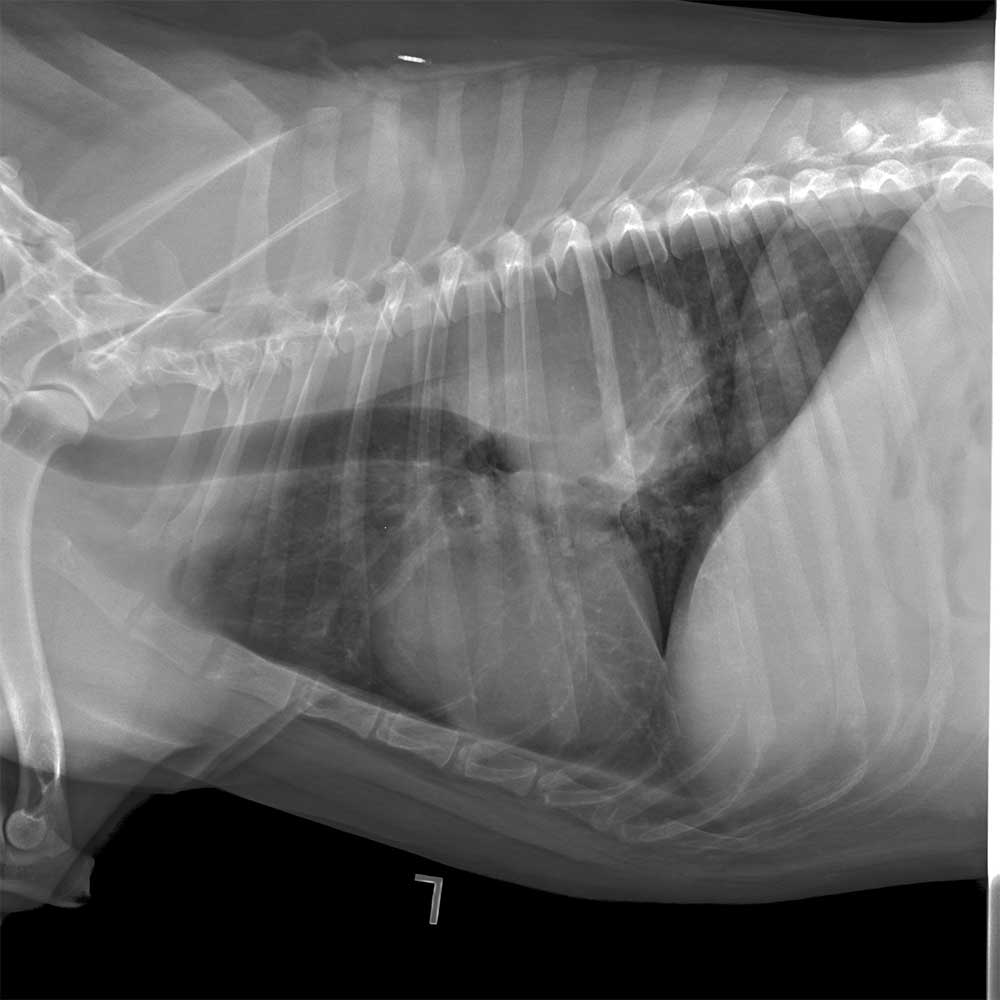

Veterinary radiography (also known as x-rays) provides an in-depth, noninvasive way to image the bones and internal organs of animals. These radiographs help veterinarians diagnose and monitor various conditions, such as bone fractures, dental issues, and internal organ problems.

The process involves positioning the animal and capturing images that can reveal abnormalities

and guide treatment decisions. Veterinary radiography is a critical tool for providing accurate and effective care to animals.